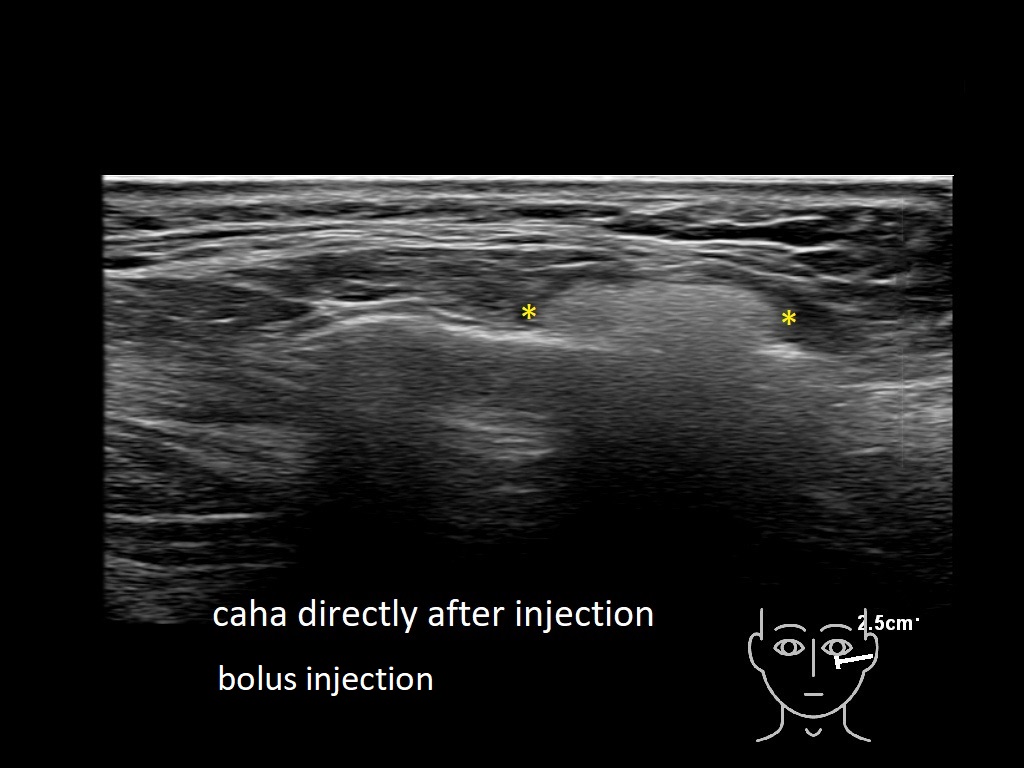

Draw in the image on the right where the fillers are located. To check if your answer is correct, please click on the secondary image.

Draw in the second image below where the fillers are located. To check if your answer is correct, swipe the first image to the right.